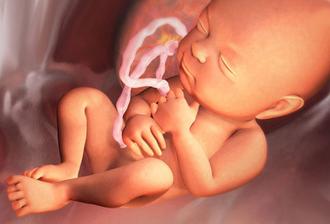

29.4. druhá KO u dr 7+3, 12,3mm a srdíčko bije